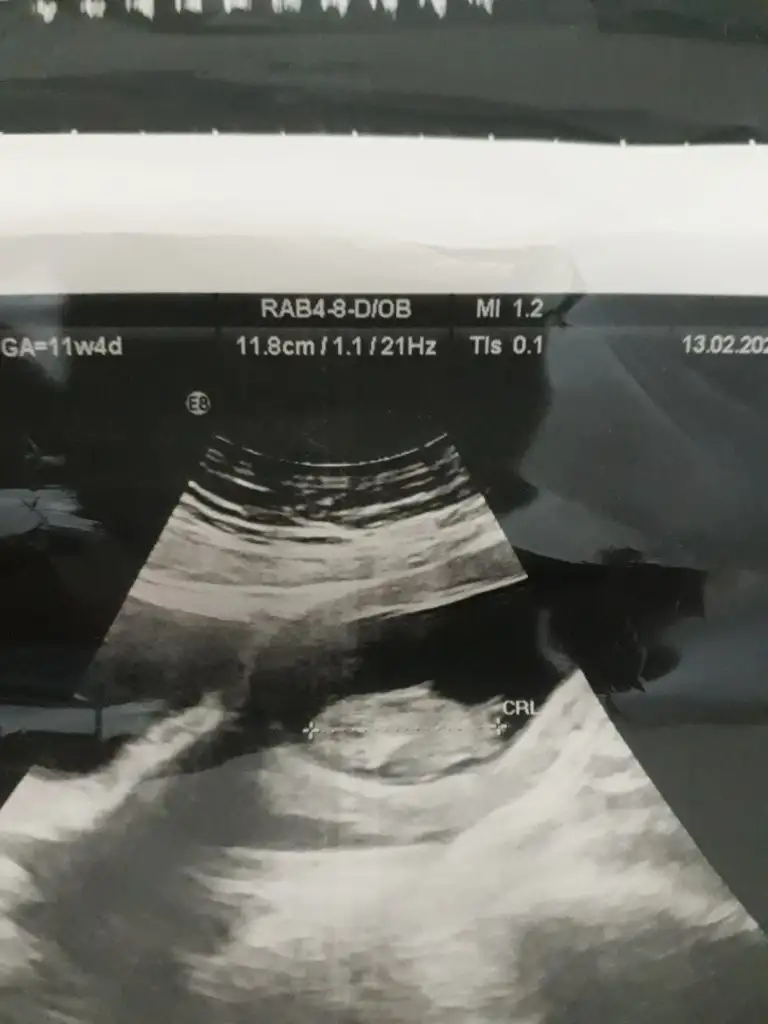

Emin olmamakla birlikte sanki kız nub tarafı çok karanlık başka usg varmı paylaşınEki Görüntüle 2590346 Eki Görüntüle 2590346 Çok belirgin değil ama 12.hafta usg mizIkra meyra Eki Görüntüle 2590346

10+4 te ki vardı ona da kız demiştinizEmin olmamakla birlikte sanki kız nub tarafı çok karanlık başka usg varmı paylaşın